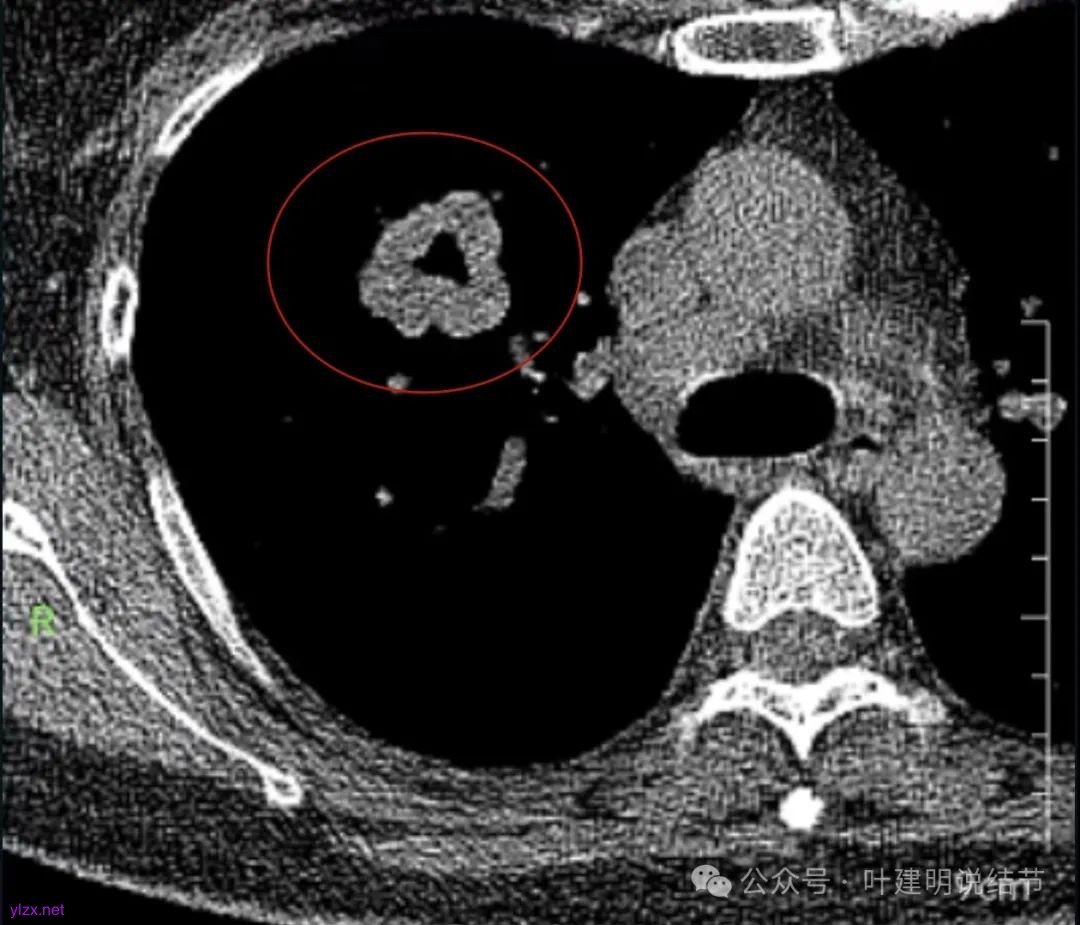

腔静脉旁明显肿大淋巴结。

你的右上叶这个病灶基本上肯定是肺癌,要尽快处理。从影像上看有以下特点:1、整体轮廓清楚,不似普通炎症的周围有晕或阻塞性改变;2、边缘明显的浅分叶,总体上的感觉膨胀性明显,不管哪个层面看上去都是鼓鼓的;3、边缘区域有磨玻璃成分而且也是分叶状的;4、部分层面见血管进入;5、空腔病灶的壁厚薄不均,内壁不光滑。我考虑中低分化肺癌,由于腔静脉旁有明显肿大淋巴结,需要进一步完善增强CT以及PET-CT检查以明确有无远处转移,是否仍可手术治疗(从病灶本身来说是可以肺叶切除治疗的)。要尽快处理。意见供参考!